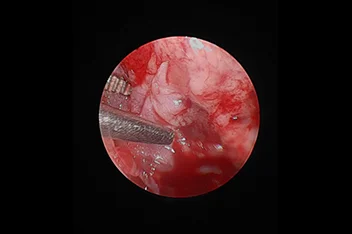

ventral slot, hemilaminectomy

• 경추 디스크